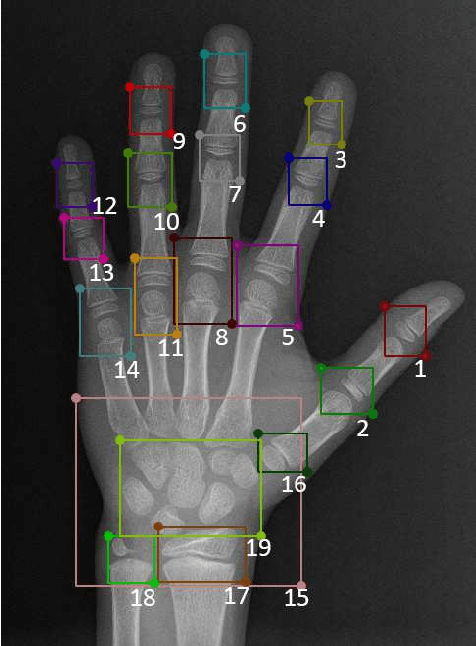

The bone age, reflecting the degree of development of the bones, can be used to predict the adult height and detect endocrine diseases of children. Both examinations of radiologists and variability of operators have a significant impact on bone age assessment. To decrease human intervention , machine learning algorithms are used to assess the bone age automatically. However, conventional supervised deep-learning methods need pre-labeled data. In this paper, based on the convolutional auto-encoder with constraints (CCAE), an unsupervised deep-learning model proposed in the classification of the fingerprint, we propose this model for the classification of the bone age and baptize it BA-CCAE. In the proposed BA-CCAE model, the key regions of the raw X-ray images of the bone age are encoded, yielding the latent vectors. The K-means clustering algorithm is used to obtain the final classifications by grouping the latent vectors of the bone images. A set of experiments on the Radiological Society of North America pediatric bone age dataset (RSNA) show that the accuracy of classifications at 48-month intervals is 76.15%. Although the accuracy now is lower than most of the existing supervised models, the proposed BA-CCAE model can establish the classification of bone age without any pre-labeled data, and to the best of our knowledge, the proposed BA-CCAE is one of the few trails using the unsupervised deep-learning method for the bone age assessment.